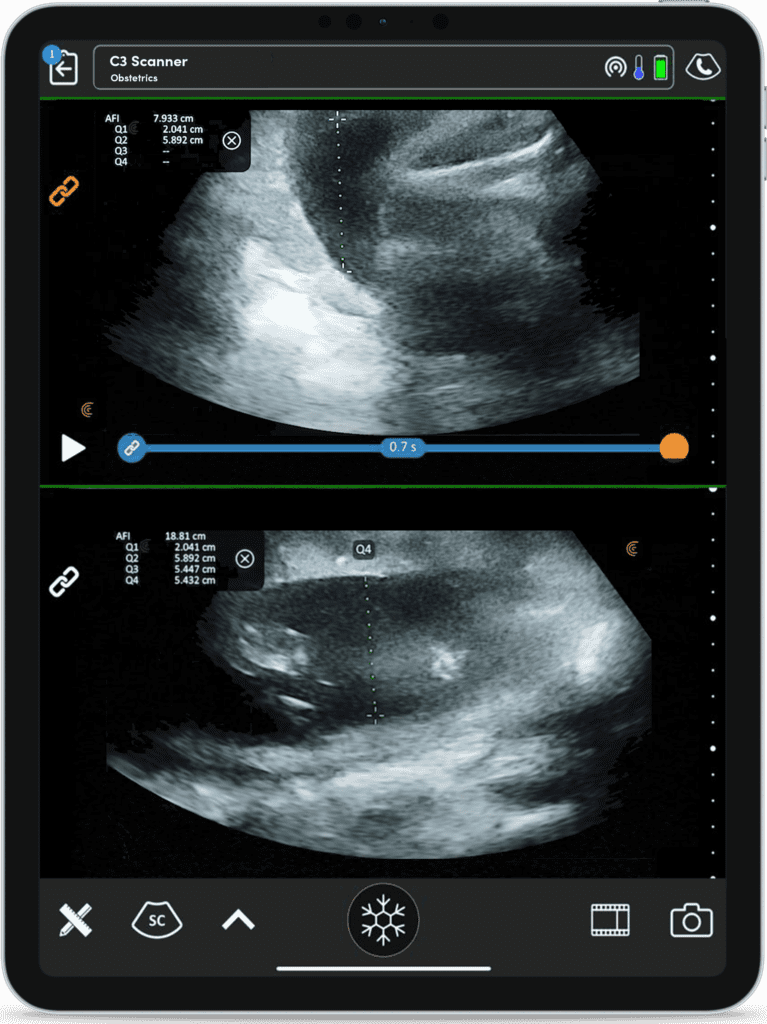

Imagerie Obstétricale Optimisée

I feel more confident with my ultrasound exams since I’ve started using OB AI. I love how the AI makes the app light up when things are perfectly lined up – I can see this really helping both seasoned clinicians and those who are starting their ultrasound journey.